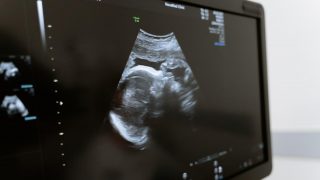

Podcast z cyklu Radia Wave Houpačky (23.11.2023) s porodní bábou Alžbětou Samkovou o potratu.

Co nás po potratu čeká v nemocnici a musíme tam vůbec? Jak přesně vypadá revize a jak o sebe pečovat v šestinedělí, které po každém potratu přichází?